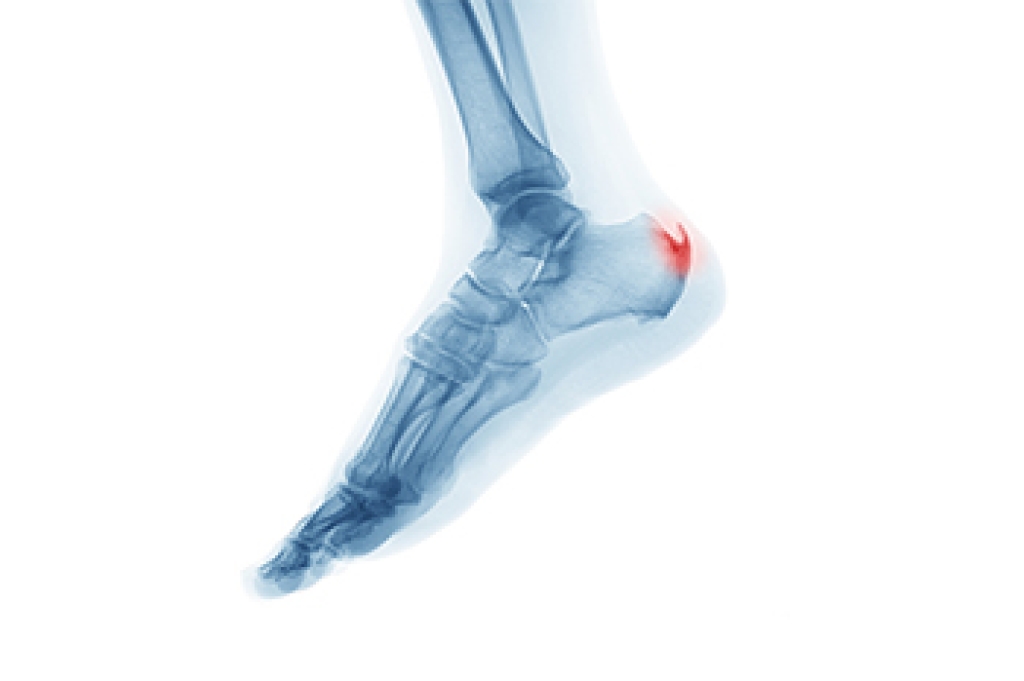

A bone spur, or osteophyte, is an extra growth onto a bone. Spurs can grow on several parts of the feet, including on top of the midfoot, on the back of the heel, or on the toe. Other bone spurs grow under the heel in conjunction with plantar fasciitis. Many people live with bone spurs and feel no pain. Surgical treatment is one way of permanently dealing with painful bone spurs. With a midfoot bump, the spur is removed from both sides of the joint involved. A surgical shoe will be needed for a few weeks after, but you can bear weight right after surgery. For a spur in the back of the heel, the spur will be removed and any damage to the Achilles tendon will be repaired. A cast and crutches will be needed for a few weeks to avoid putting weight on the foot. With a spur on the toe, a small incision will be made before the filing down of the spur with a type of rasp. The site will be bandaged and a surgical shoe may be provided, but weight bearing is OK. For help with painful bone spurs, it is wise to consult with a podiatrist for the right treatment options.

To figure out the cause of foot pain, podiatrists utilize several different methods. This can range from simple visual inspections and sensation tests to X-rays and MRI scans. Prior medical history, family medical history, and any recent physical traumatic events will all be taken into consideration for a proper diagnosis.